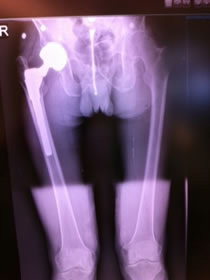

Dr. Testerman's cas is a forty-five year old female, morbidly obese with bilateral hip disease. She is currently household ambulatory and otherwise confined to a wheel chair, although able to independently transfer herself to and from bed. X-rays show destructive bilateral OA of the hip with such severity it is hard to determine if the underlying disease is hip dysplasia or not. The right hip head has collapsed making true measurement of femoral offset difficult.

Due to her relative young age, body weight and the likely fact that she will be facing one or more revisions in her lifetime Dr. Testerman decided a more bone conservative tissue sparing approach would be in her best interest. Although her body weight certainly did not lend itself to a conservative soft tissue approach this device does not require resection into the greater trochanteric and abductor musculature area.

At 5' 2" and 250 lbs this was going to be a challenge for any approach, devise, and surgeon. In addition this was being done at a new hospital with a new team that had not seen this devise before. Prior to surgery, John and I had a chance to review the x-rays and we did not see anything that should hinder the selection of the ARCTM Stem. We did have a conventional stem on backup and always recommend that a conventional stem be available. I did suggest that he take an intraoperative x-ray once the trials were implanted.

| X-ray confirmed our impression that we could go up in size of the stem and neck length. The offset appeared to be good with a neutral modular neck and 0 head with a 36 mm poly insert. |